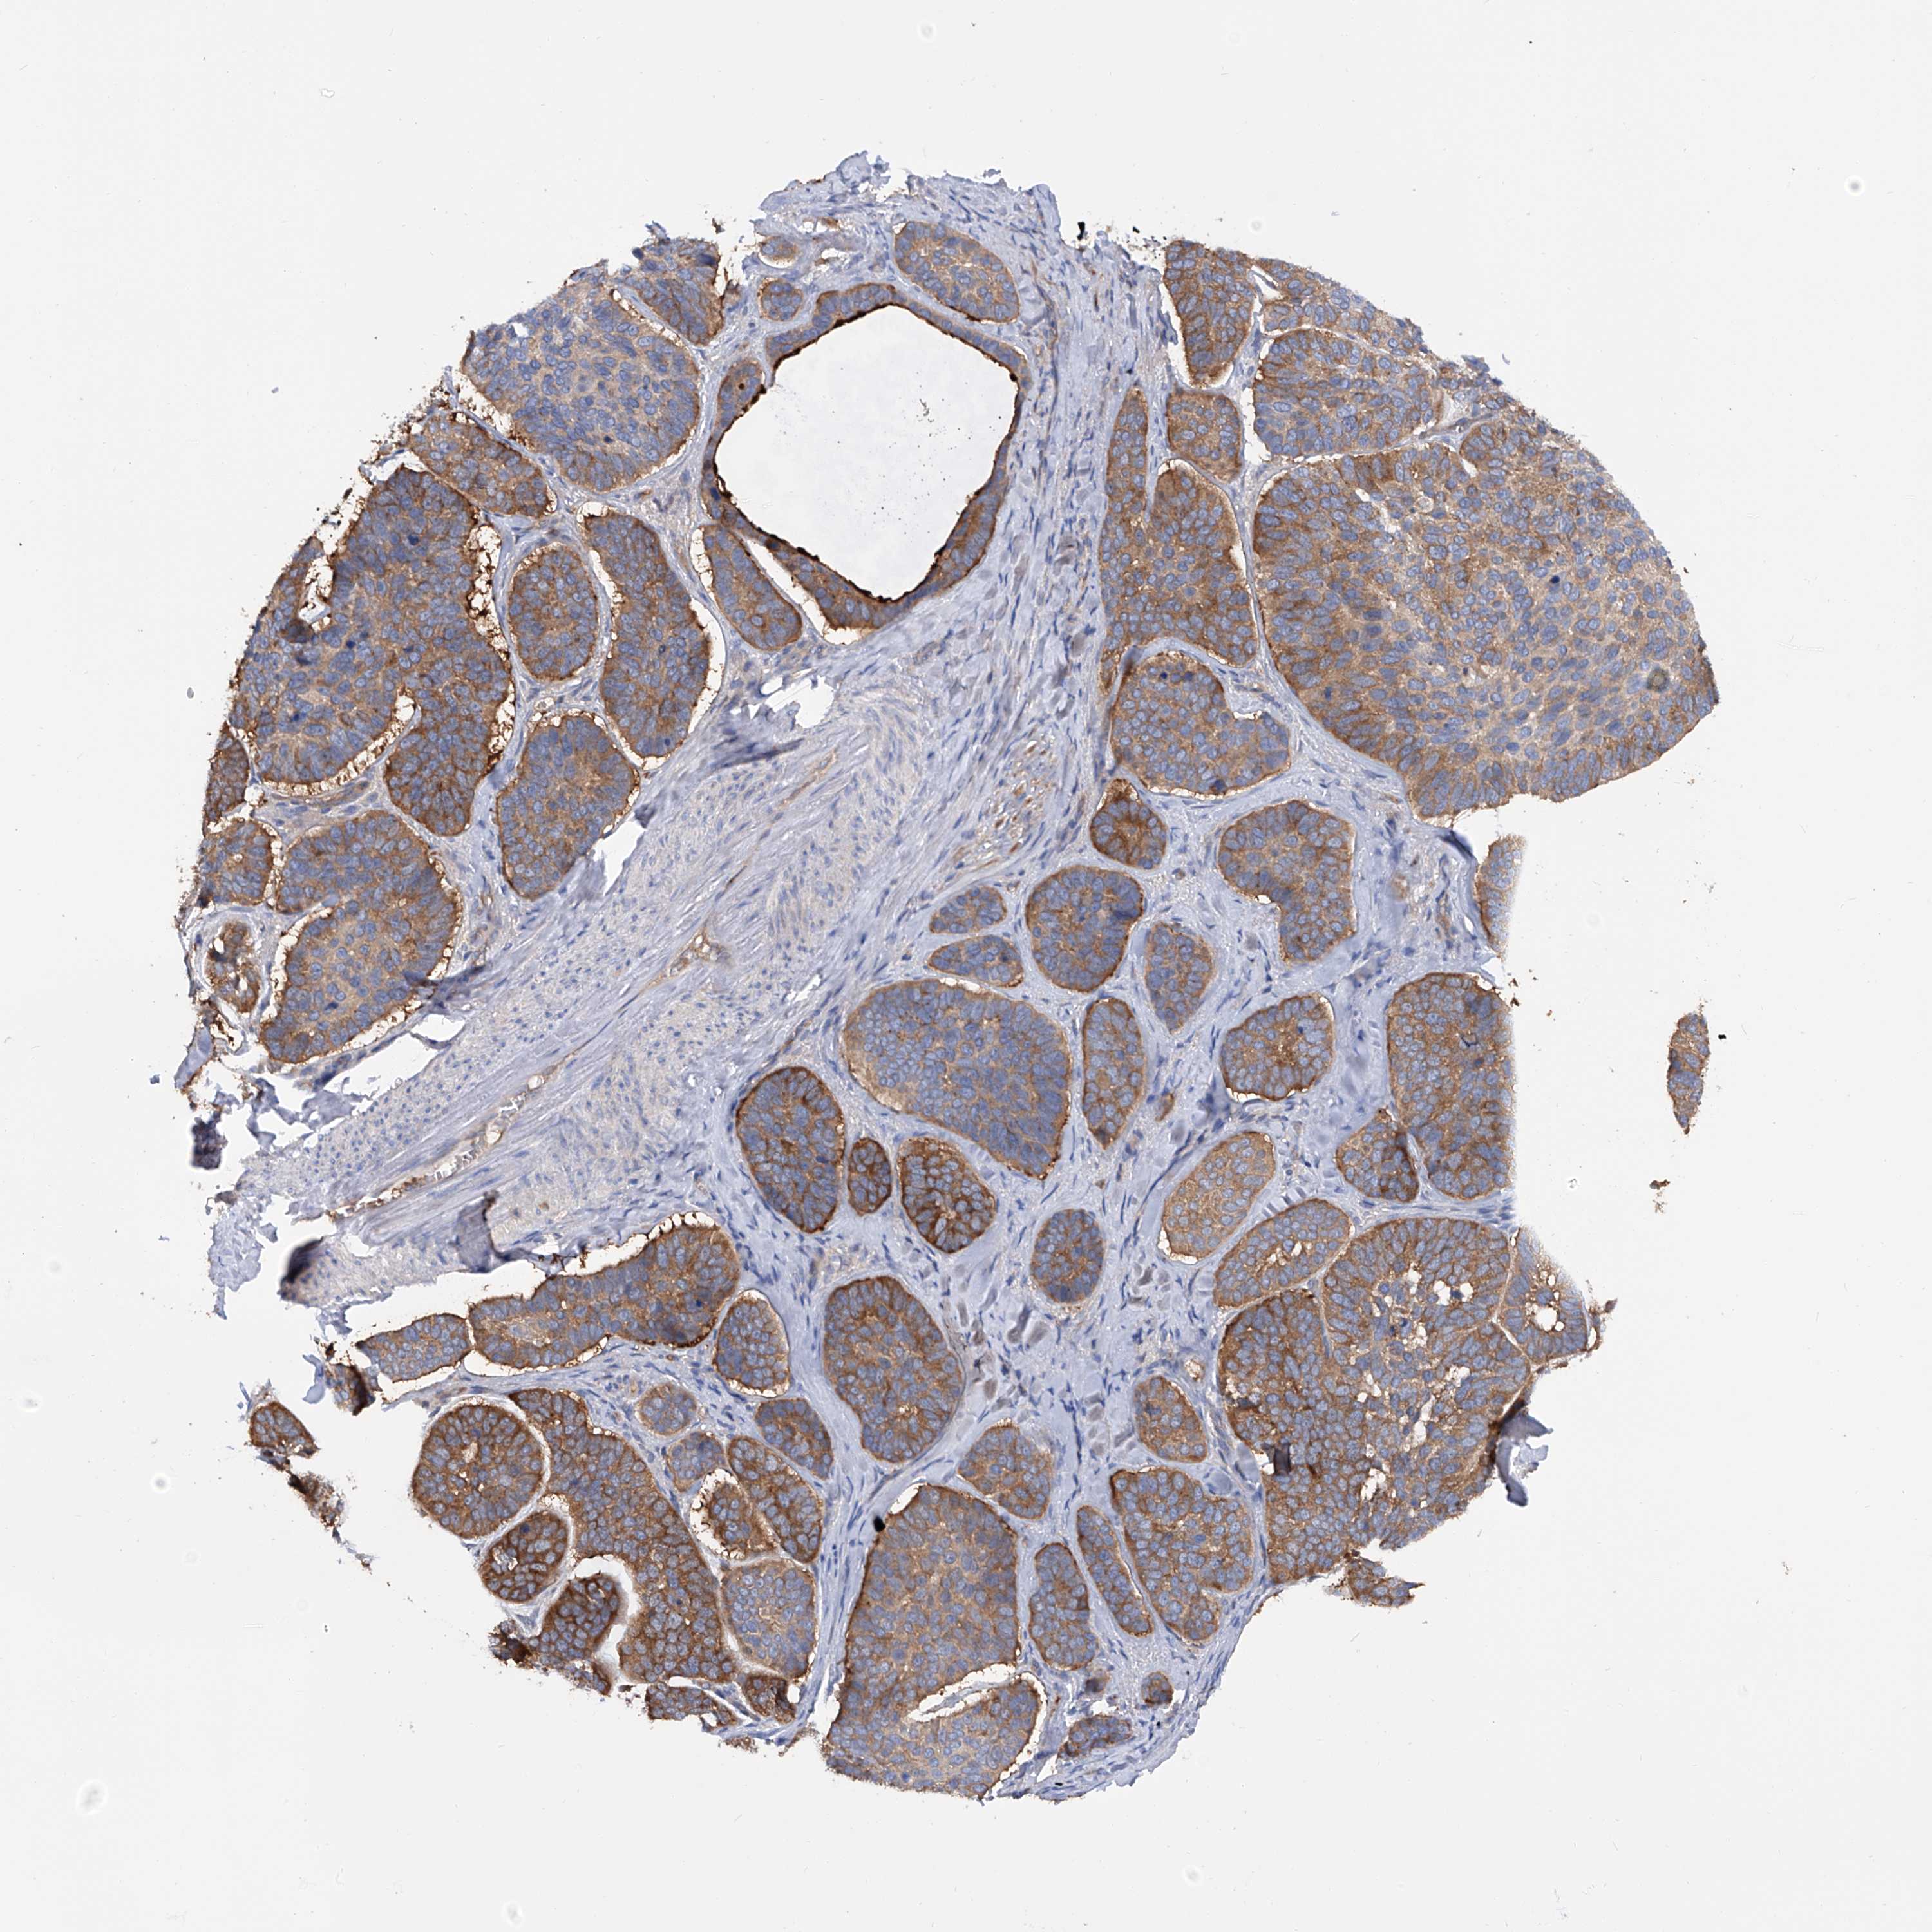

Basal cell and squamous cell cancer

SKIN CANCER - Protein expressioni

A mouse-over function shows sample information and annotation data. Click on an image to view it in a full screen mode. Samples can be filtered based on level of antibody staining by selecting one or several of the following categories: high, medium, low and not detected. The assay and annotation is described here.

Antibody stainingi

Antibody staining in the annotated cell types in the current human tissue is reported as not detected, low, medium, or high, based on conventional immunohistochemistry profiling in selected tissues. This score is based on the combination of the staining intensity and fraction of stained cells.

Each image is clickable and will lead to virtual microscopy that enables deeper exploration of all samples and also displays staining intensity scores, fraction scores and subcellular localization as well as patient and tissue information for each sample.

Antibody HPA030145

Staining

High

Medium

Low

Not detected

Intensity

Strong

Moderate

Weak

Negative

Quantity

>75%

75%-25%

<25%

None

Location

Nuclear

Cytoplasmic/membranous

Cytoplasmic/membranous,nuclear

Squamous cell carcinoma, NOS